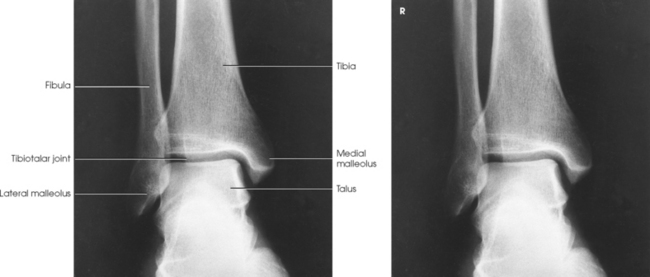

The ankle joint is commonly called the ankle mortise, or mortise joint. It is formed by the articulations between the lateral malleolus of the fibula and the inferior surface and medial malleolus of the tibia (Fig. 6-13, A). The mortise joint is often divided specifically into the talofibular and tibiofibular joints. These form a socket type of structure that articulates with the superior portion of the talus. The talus fits inside the mortise. The articulation is a synovial hinge type of joint. The primary action of the ankle joint is dorsiflexion (flexion) and plantar flexion (extension); however, in full plantar flexion, a small amount of rotation and abduction-adduction is permitted. The mortise joint also allows inversion and eversion of the foot. Other movements at the ankle largely depend on the gliding movements of the intertarsal joints, particularly the one between the talus and calcaneus.

Structures shown: The image shows a true AP projection of the ankle joint, the distal ends of the tibia and fibula, and the proximal portion of the talus.

NOTE: The inferior tibiofibular articulation and the talofibular articulation are not “open” or shown in profile in the true AP projection. This is a positive sign for the radiologist because it indicates that the patient has no ruptured ligaments or other type of separations. For this reason, it is important that the position of the ankle be anatomically “true” for the AP projection shown (Fig. 6-92).